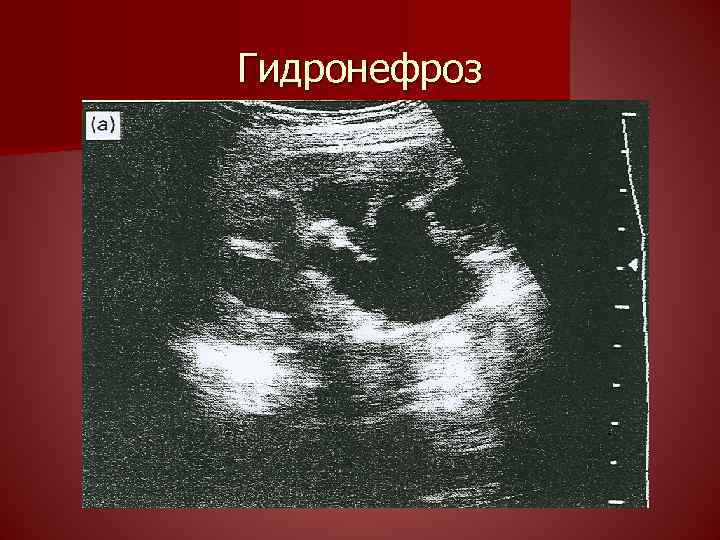

Порок мочеполовой системы 114 фотографий